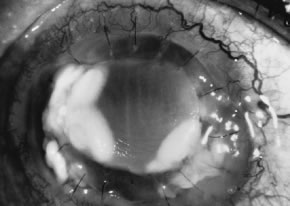

There is no distinguishing clinical sign by which to recognize the genus or species of the infectious filamentous fungus. F. solani is the most virulent organism and typically produces rapidly progressive infection characterized by epithelial and stromal ulceration, dense stromal necrosis, abundant cellular infiltrate, and edema in the adjacent stroma and hypopyon (Figs. 8 and 9). Delicate feathery components are transient. Individual hyphal fragments are rarely visualized. Infection by certain species of Aspergillus and Scedosporium (Figs. 10 and 11) resembles F. solani keratitis and progresses rapidly. Infection by less virulent organisms, such as Curvularia and Alternaria species, produces small, focal (less than 3-mm diameter) areas of nonnecrotizing stromal inflammation with delicate feathery borders (see Fig. 1 and Fig. 12). Macroscopic pigmentation may develop in keratitis caused by Alternaria, Curvularia, and other dematiaceous fungi (Fig. 13).4,11,14 The central component may progress to dense, opaque, gray-white suppuration in the deep stroma without enlargement in total area and may be accompanied by mild inflammation in the adjacent stroma. Iritis is minimal to moderate. Infection caused by other, relatively less virulent organisms resembles herpes simplex or noninfectious keratitis (Fig. 14).

Fig. 10. Scedosporium apiospermum keratitis in a 53-year-old woman, 10 days following unknown foreign body injury while gardening. Epithelial and stromal ulceration, endothelial plaque, and hypopyon. Note the corneal edema surrounding the central area of suppuration.

Fig. 11. Scedosporium apiospermum keratitis. Note the dense, suppurative stromal keratitis and hypopyon.